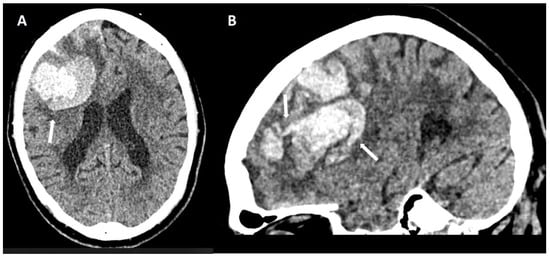

5.1.1. Lobar Hemorrhages

6.2. Subarachnoid Extension of Lobar Hemorrhage

- Baron, J.-C.; Boulouis, G.; Benzakoun, J.; Schwall, C.; Oppenheim, C.; Turc, G.; Varlet, P. Cerebral amyloid angiopathy-related acute lobar intra-cerebral hemorrhage: Diagnostic value of plain CT. J. Neurol. 2022, 269, 2126–2132. [Google Scholar] [CrossRef]

- Rodrigues, M.A.; Samarasekera, N.; Lerpiniere, C.; Humphreys, C.; McCarron, M.O.; White, P.M.; Nicoll, J.A.R.; Sudlow, C.L.M.; Cordonnier, C.; Wardlaw, J.M.; et al. The Edinburgh CT and genetic diagnostic criteria for lobar intracerebral haemorrhage associated with cerebral amyloid angiopathy: Model development and diagnostic test accuracy study. Lancet Neurol. 2018, 17, 232–240. [Google Scholar] [CrossRef]

- Baron, J.-C.; Jensen-Kondering, U.; Sacco, S.; Posener, S.; Benzakoun, J.; Pallud, J.; Oppenheim, C.; Varlet, P.; Turc, G. Can novel CT-and MR-based neuroimaging biomarkers further improve the etiological diagnosis of lobar intra-cerebral hemorrhage? J. Neurol. 2023, 270, 582–588. [Google Scholar] [CrossRef]